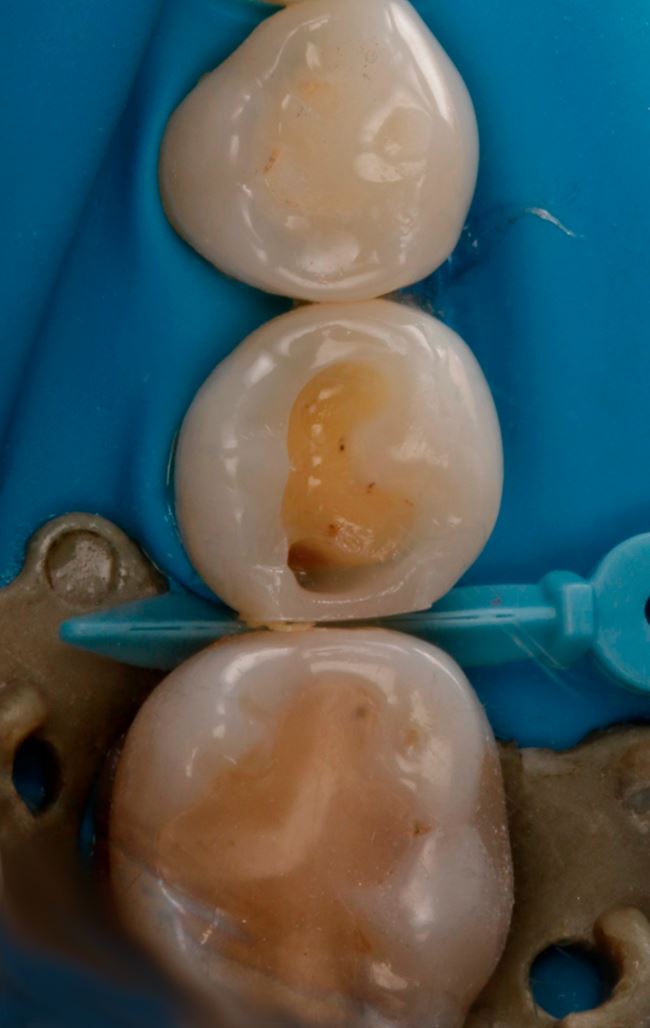

Ubytek na powierzchni dystalnej okazuje się całkiem duży, obejmuje znaczną część zębiny. Teraz nie ma już wątpliwości, że bez wypełnienia się nie obejdzie, a więc podajemy znieczulenie, zakładamy koferdam (ryc. 7) i przystępujemy do opracowania. Po usunięciu amalgamatu w dystalnej części ubytku widać ciemniejszą zębinę (ryc. 8). Usuwamy dystalną listewkę szkliwa i już widać wyraźne odwapnienie (ryc. 9). Dalej jest tylko ciemniej i głębiej (ryc. 10 i 11).

Ryc. 7. Ząb 45 przed usunięciem wypełnienia amalgamatowego.

Ryc. 8. Ząb 45 po usunięciu wypełnienia amalgamatowego.

Ryc. 9. Ząb 45 po częściowym otwarciu ubytku.

Ryc. 10. Ząb 45 z częściowo opracowanym ubytkiem próchnicowym kl. II D.

Ryc. 11. Ząb 45 po opracowaniu ubytku kl. II D.